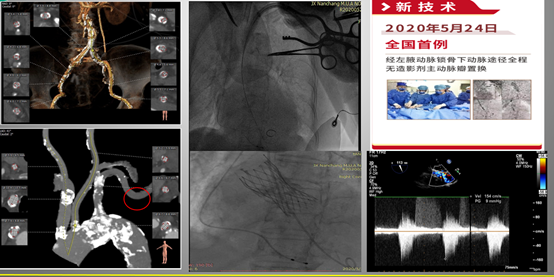

然而,当患者存在股动脉管腔严重狭窄、血管显著迂曲或重度钙化等不适合TF入路的情况时,应考虑采用其他替代入路策略,包括颈动脉入路、锁骨下/腋动脉入路、经心尖入路、经升主动脉入路以及经腔静脉入路等。

经腋动脉入路无造影剂TAVR